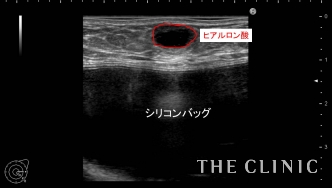

他院にてヒアルロン酸豊胸・バッグ豊胸を受けられ、その直後からしこりが触れはじめたとのこと。豊胸を受けたクリニックでは取り合ってもらえず、更に他院へ相談するがバッグが入っているため処置は難しいと言われ、当院を受診されました。 しこりの大きさは1cmですが、被膜を形成しています。

ヒアルロン酸のしこりのすぐ下にシリコンバッグ がありますのでバッグを損傷しないように注意する必要があります。 エコー下にて確実にヒアルロニダーゼをしこり内に注入し、その後ヒアルロン酸を吸引除去します。

吸引後、エコーにてしこりの消失を確認しました。 ヒアルロン酸のしこりはエコー下に行えば 、安全に確実に治療することが可能です。